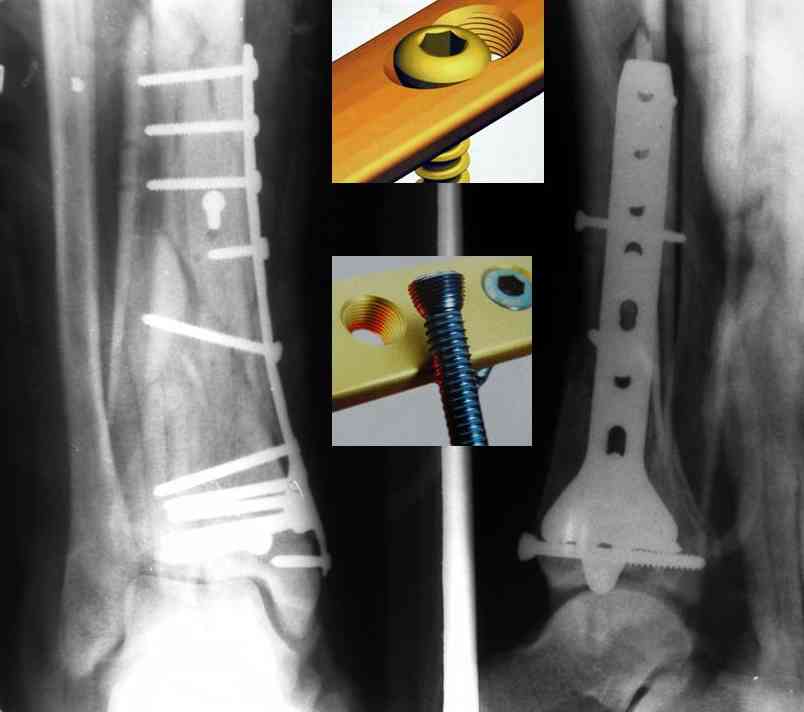

Re: Perelom N/3 kostei goleny

послал Дрягин В. 04 Январь 2007, 09:01

Послала ещё два снимка, если не пройдут, пошлю ещё. Дрягин. Если есть вопросы, готов ответить.